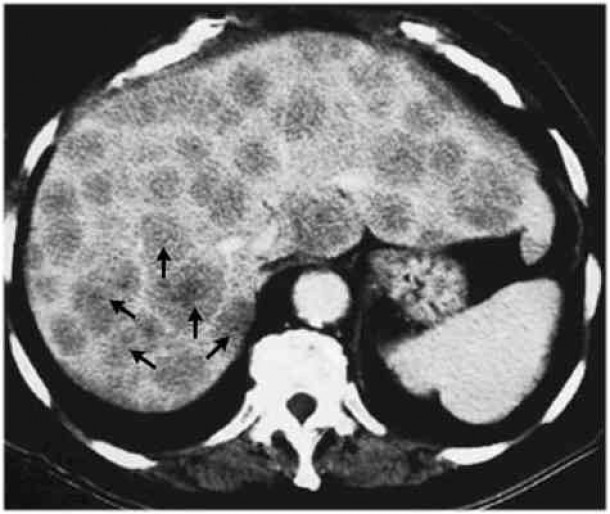

Raziskovalke in raziskovalci so najprej odvzeli maligno tkivo ljudem s tumorjem črevesja in z metastazami v jetrih. Preučevali so, ali se bakterija Fusobacterium nucleatum, ki jo tumorske formacije najpogosteje vsebujejo, pojavlja v obeh tipih tumorjev. Potrdili so svojo domnevo, da se pri večini bolnikov v črevesnem in jetrnem tumorju nahaja isti sev te bakterije. Veljalo je tudi nasprotno; če bakterij ni bilo v črevesnem tumorju, jih ni bilo tudi v jetrnem.

V drugem delu so črevesne tumorje ljudi vsadili v črevesje zdravih podgan. Opazili so, da so tumorji z bakterijami »uspevali« v podganah, tisti brez njih pa ne. Zdravljenje z antibiotikom metronidazolom, ki deluje proti bakteriji Fusobacterium nucleatum, pa je zmanjšala bakterijsko breme in upočasnila rast tumorja.